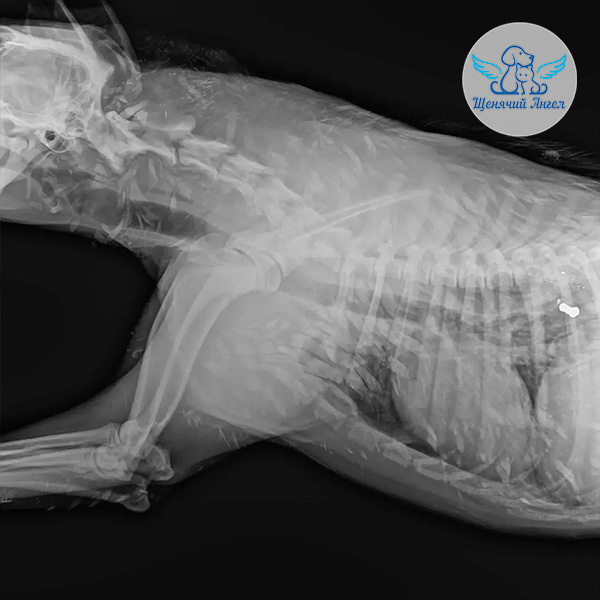

По прибытии в клинику Нео сразу прошёл полное обследование: его осмотрел хирург, был выполнен рентген и взяты необходимые анализы на инфекции ⚕️

По результатам диагностики в области рёбер с обеих сторон обнаружены входные отверстия от пуль без образования полостей, с небольшими кровянистыми выделениями.

🩻 Рентген показал, что одна из пуль остаётся в теле – она расположена под кожей справа. Жизненно важные внутренние органы не задеты 🙏🏻